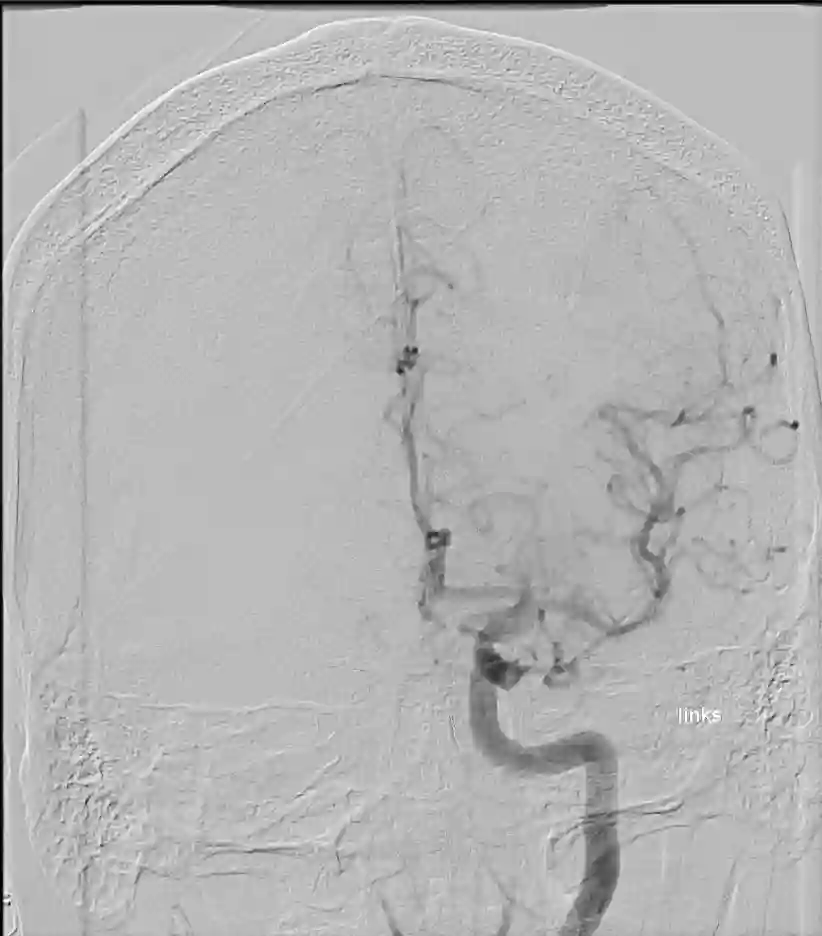

Angiographie

ICA Angiographie mit Knochen

Darstellung einer ICA digitalen Subtraktionsangiographie mit knöchernen Strukturen des Schädels.